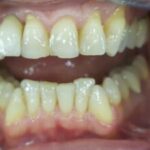

Vorher: Alte Implantat-Krone kleinerer Schneidezahn ; nicht ansprechende Ästhetik Frontzähne

Nachher